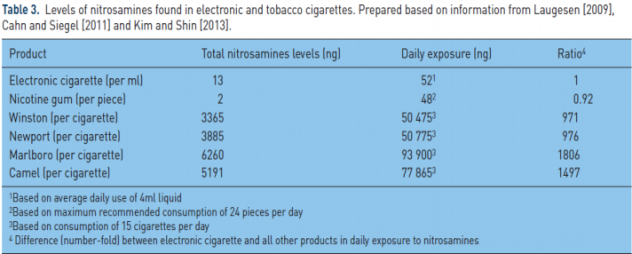

Начал Доктор Фарсалинос с химических исследований. Согласно этим исследованиям, нитрозамины являются главными канцерогенами, которые содержатся в обычных табачных сигаретах. В таблице снизу отображено содержания нитрозаминов в электронных сигаретах, никотиновой жвачке и разных брендах табачных сигарет, снизу вверх, в первом столбце соответственно. Во втором столбце отображено количество нитрозаминов в 1 мл жидкости для электронных сигарет, одной никотиновой жвачке и одной сигарете соответственно. В третьем — суточное потребление. Результат налицо: